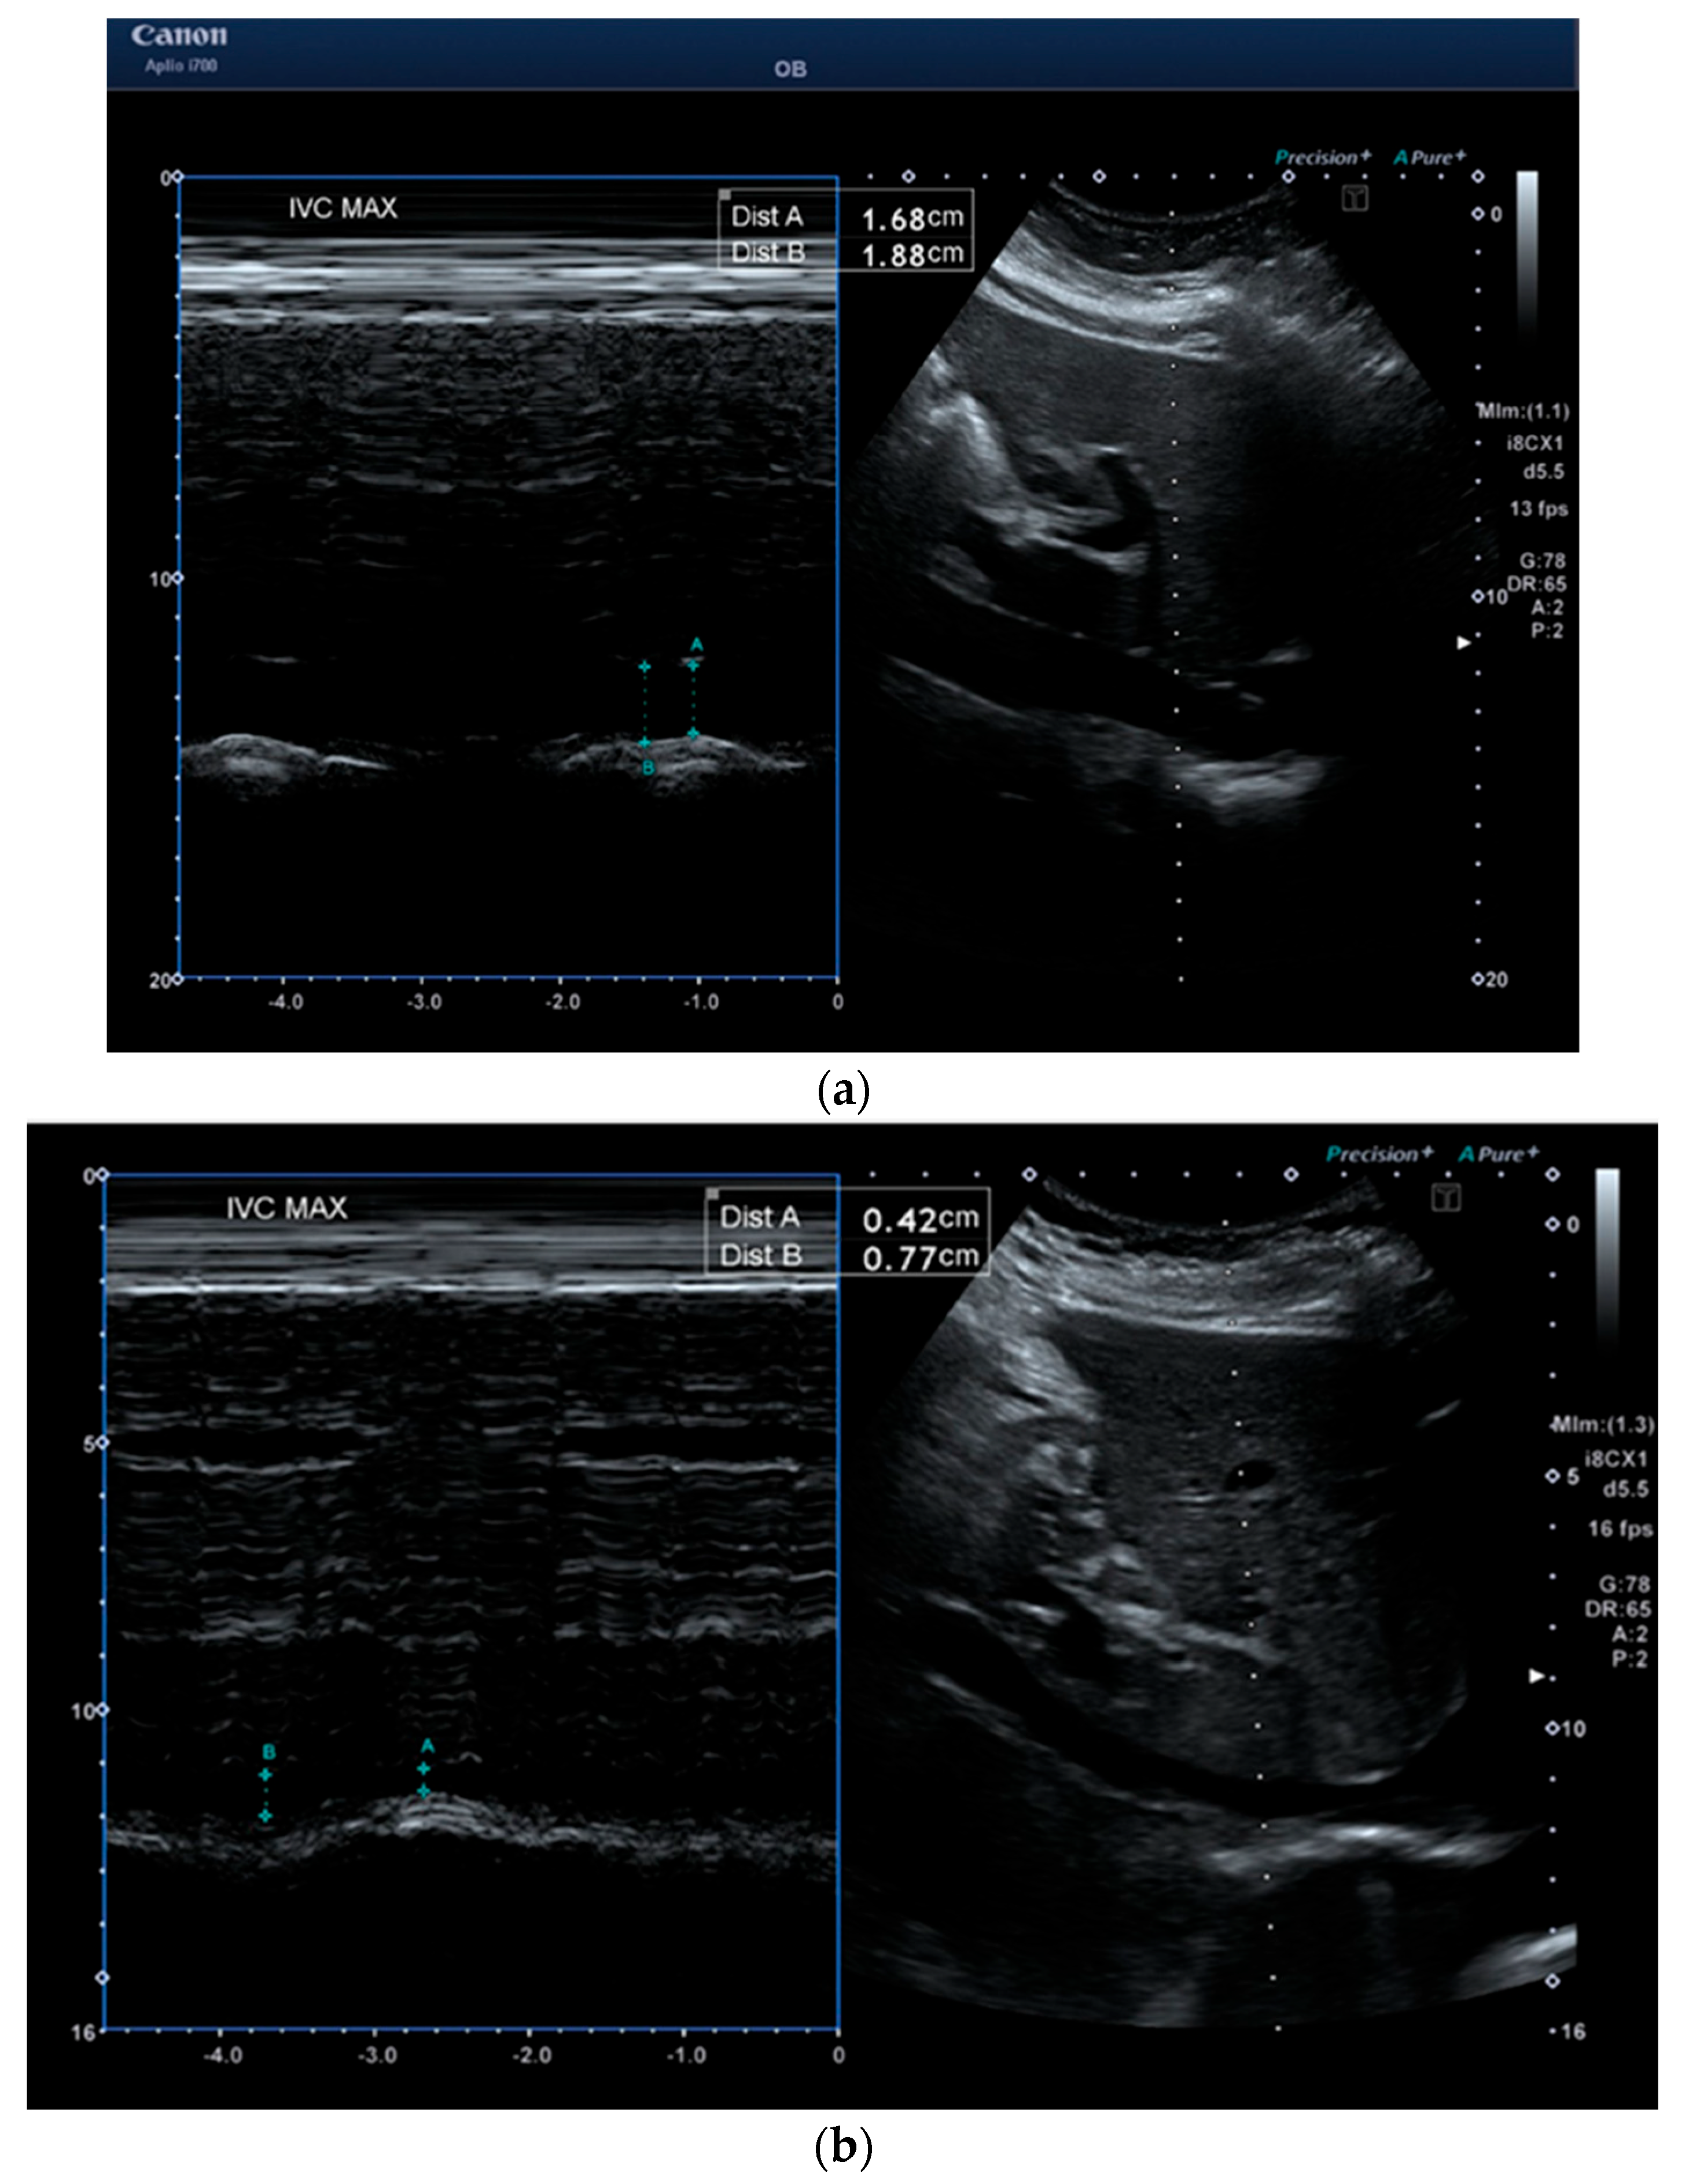

| IVC inhalation (cm) | 0.6 (0.2) | 1.5 (0.4) | p < 0.001 |

| IVC exhalation (cm) | 1.1 (0.3) | 1.9 (0.3) | p < 0.001 |

| IVC-CI (%) | 48.3 (13.6) | 20.1 (14.5) | p < 0.001 |